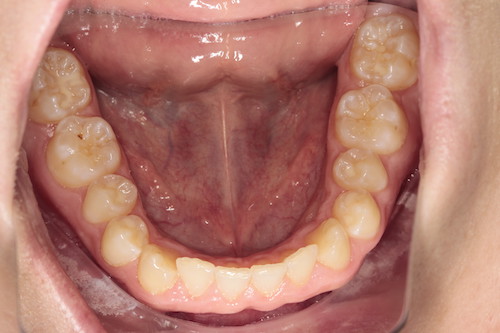

Частая ситуация, когда в общем все не плохо, но чего- то не хватает для идеала. Основной жалобой пациента было наличие выраженных промежутков на верхней челюсти, неровность положения зубов, глубокое перекрытие передних нижних резцов. Причина наличия промежутков заключалась в недостаточном размере по ширине боковых резцов верхней челюсти. именно поэтому после подъема высоты прикуса, нормализации наклонов зубов в переднем отделе, коррекции высоты перекрытия резцов, и доведение идеальных контактов в боковых отделах мы увеличили размер боковых резцов за счет композитного материала. Срок лечения 1 год.

После